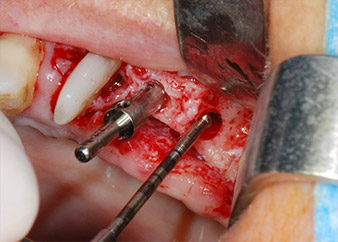

Im folgenden Schritt wurde das jeweilige Implantatbett an den Positionen 25 und 26 mit rotierenden Instrumenten in einem Winkelstück mit einem Übersetzungsverhältnis von 20:1 (WS-75 L G, W&H) und einem vor Kurzem aktualisierten leistungsstarken Implantatmotor präpariert (Implantmed, W&H) (Abb. 8 und 19).

Dann wurden die Implantate (Restore, Keystone Dental) mit dem Implantatmotor eingesetzt (Abb. 11 und 12).